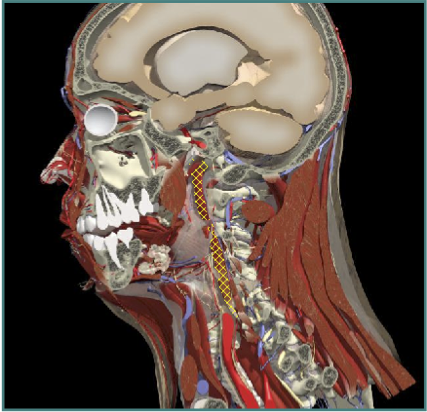

ACCURACY OF LOCALIZATION - SCALENES

ACCURACY OF LOCALIZATION LEVATOR SCAPULAE

LOCALIZATION OF MUSCLES IN DEEPER LAYERS

INJECTION SITES